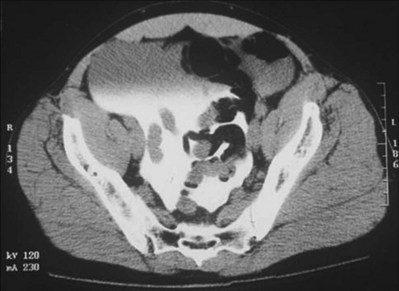

Although both cellulitis and Fournier gangrene are commonly associated with significant genital edema and erythema, skin ischemia is the hallmark of Fournier gangrene. The finding of loss of scrotal rugae is highly suggestive of tissue necrosis. Scrotal ultrasonography (Kane et al, 1996) and computed tomography (CT) may reveal subcutaneous air, a helpful indicator of necrotizing infection (Fig. 88–7).

Figure 88–7 A, Large erythematous scrotum with central necrosis suggestive of necrotizing infection. B, CT reveals subcutaneous air in scrotum (arrow) secondary to Fournier gangrene.